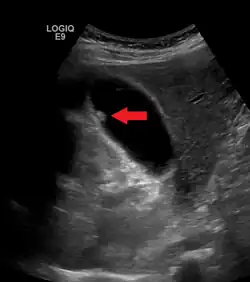

Adenomyomatosis describes a diseased state of the gallbladder in which the gallbladder wall is excessively thick, due to proliferation of subsurface cellular layer. It is characterized by deep folds into the muscularis propria. Ultrasonography may reveal the thickened gallbladder wall with intramural diverticulae, called Rokitansky-Aschoff sinuses.[3]

Diagnosis is typically by ultrasound or CT imaging.

Ultrasound image of gallbladder polyps measuring 3–7 mm. -